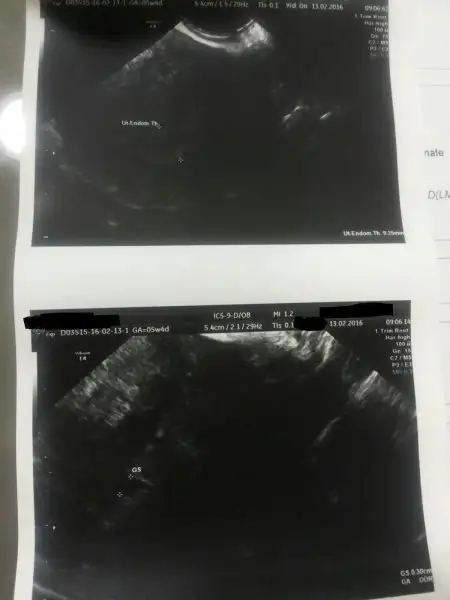

şimdi ilk resim şu 5+4 gittim değer 1112 idi , doktor dediki keseye benzer bişi var. ama bunu raporunda kist olarak değerlendirmiş ve bana resmen fitili attı dış gebelik şüphelisin diyerekten 1 hafta nasıl geçti bilmiyorum

şimdide 6+4 gittiğim doktor bunu verdi dediki sandıgınız kadar buyuk bı gebelık degıl bu dedı. cok saglıklı gozukuyor dedı ayrıca 5+4 tekı doktorun raporund asoyle yazıyordu

düzensiz sınırlı anekoık gorunumlu beta ve usg takıp.